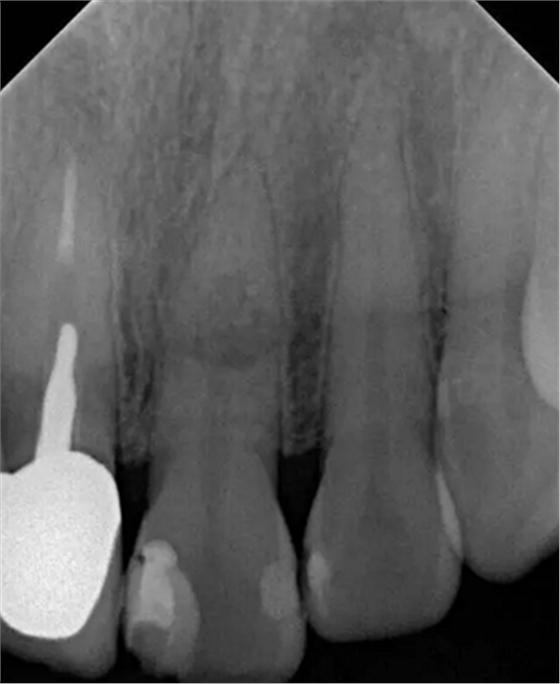

左上中切牙近遠(yuǎn)中有牙色充填體,邊緣繼發(fā)齲,牙齒不松動(dòng),輕微叩痛,患牙冷測遲鈍,牙齦未見異常。X線片示:充填體周圍繼發(fā)齲壞近髓,根中部大面積低密度影,蟲噬狀,內(nèi)部結(jié)構(gòu)顯示不清晰,根尖周未見異常。錐形束CT(CBCT)顯示根中部內(nèi)吸收多處可疑穿孔,缺損內(nèi)可見菜花狀鈣化物影像

診斷:左上中切牙牙根內(nèi)吸收。治療計(jì)劃:左上中切牙根管治療,全冠修復(fù)。 治療過程:患者知情同意。使用含1/100,000腎上腺素的4%鹽酸阿替卡因(碧蘭麻,艾龍)局部浸潤麻醉,橡皮障隔濕。去腐未盡露髓,露髓孔出血多。開髓,使用10#不銹鋼K銼(MANI,日本)探查根管,根管中段有鈣化物阻擋,不能達(dá)到牙根全長(圖3A)。在顯微鏡下(Leica M400E,萊卡, 德國) 使用超聲尖(E1根管治療超聲尖,啄木鳥公司,中國)通開,采用根管長度測量儀(Root ZX, Morita公司,日本)加診斷絲片法(圖1B)測量根管長22 mm。使用控制扭矩馬達(dá)(X-smart,登士柏)和鎳鈦旋轉(zhuǎn)器械(Hero 642, Micromega)根管預(yù)備,根管預(yù)備過程中使用5.25%次氯酸鈉溶液沖洗。 根備完成后使用超聲蕩洗根管,5.25%次氯酸鈉溶液3 分鐘, 17% EDTA溶液1分鐘。干燥根管,使用螺旋充填器根管內(nèi)封氫氧化鈣糊,氧化鋅丁香油水門汀暫封。1周后患者復(fù)診,患者述無術(shù)后不適,檢查暫封完好,無叩痛,不松,牙齦無紅腫瘺管。使用橡皮障隔濕,去除暫封物,超聲蕩洗根管,5.25%次氯酸鈉溶液3 分鐘, 17% EDTA溶液1分鐘。干燥根管,牙膠尖(達(dá)雅鼎,中國)和必蘭根充糊劑(Cortisomol, 艾龍公司,法國)熱垂直加壓法根管充填。術(shù)后片顯示根充恰填,可見牙膠/糊劑被壓入鈣化物周圍和內(nèi)部縫隙內(nèi)